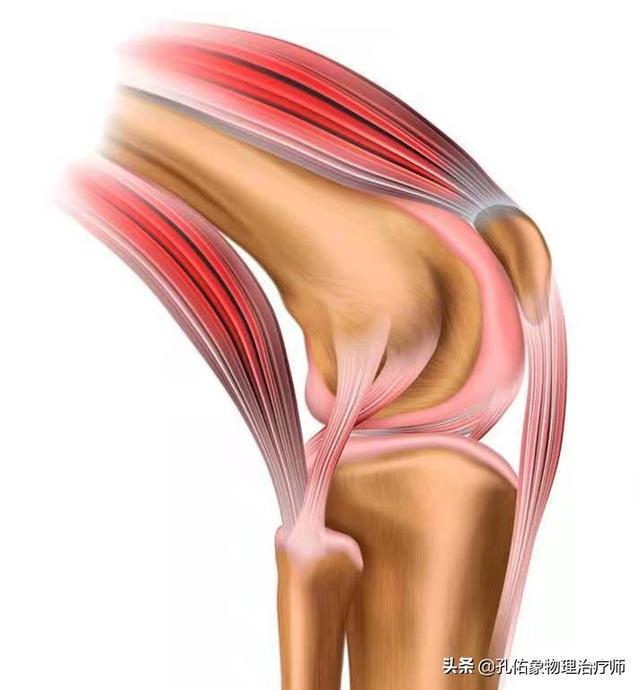

La maladie ne concerne pas seulement les os, les articulations et le cartilage articulaire, mais aussi les tendons, les ligaments et les rotules autour de l'articulation du genou, qui sont irrités par la tension et l'inflammation, ce qui provoque des douleurs et une gêne.

La plus courante est l'arthrose du genou, qui est principalement causée par des changements dégénératifs du cartilage articulaire et des ostéophytes secondaires. Le principal symptôme de cette maladie est une douleur dans l'articulation du genou, qui s'aggrave avec l'activité et s'améliore avec le repos. La zone autour de l'articulation est froide et il est souvent nécessaire de porter des genouillères pour la maintenir au chaud. Gonflement et limitation des mouvements. Dans les cas graves, on observe une inversion du genou ou une déformation en valgus.

L'articulation du genou est unique dans la manière dont elle supporte le poids, et la charge qu'elle subit augmente considérablement lorsque nous nous engageons dans des activités sociales et sportives. Pour que l'articulation du genou soit à la fois souple et capable de tolérer des charges importantes, la structure complexe des muscles environnants est essentielle. Les genoux froids et douloureux, ainsi que les craquements, s'expliquent bien par la structure de l'articulation du genou.

Nous nous appuyons sur nos deux jambes pour marcher, nous devons donc étendre les articulations de nos genoux pour nous aider à déplacer notre centre de gravité. Le genou peut être fléchi vers l'arrière, mais il n'y a en principe pas de mobilité vers l'avant et vers les côtés afin de maintenir la stabilité de nos articulations du genou. La base du maintien de cette stabilité repose sur les quatre éléments indispensables de l'articulation du genou :

(i) le muscle quadriceps comme source d'énergie ; (ii) la rotule ; (iii) le tendon rotulien ; et (iv) le point d'action de la tubérosité tibiale.

En général, plus la zone est proche du cœur, plus elle est chaude, tandis que la température à l'extrémité du membre est relativement plus froide. Cela est lié à notre circulation sanguine : la température est plus élevée dans les zones riches en sang, alors que l'articulation du genou n'est pas vraiment riche en sang du côté antérieur, sauf du côté postérieur.

Il est donc normal que l'articulation du genou soit froide, mais la personne moyenne ne remarquera pas que l'articulation du genou est froide. Si l'activité articulaire d'une personne est réduite, la circulation sera moins bonne, les articulations deviendront raides, en particulier chez les personnes âgées qui ont à l'origine une mauvaise circulation par rapport aux jeunes, si l'activité est également moindre, la circulation autour des articulations est encore plus mauvaise, vous sentirez que les articulations sont froides.

Et ce froid ne peut pas simplement toucher le froid, mais peut aussi montrer le froid dans l'os, la sensation de douleur, ici la douleur est tout à fait appropriée pour la médecine chinoise "la douleur ne passe pas" pour décrire la mauvaise circulation conduit à la douleur.